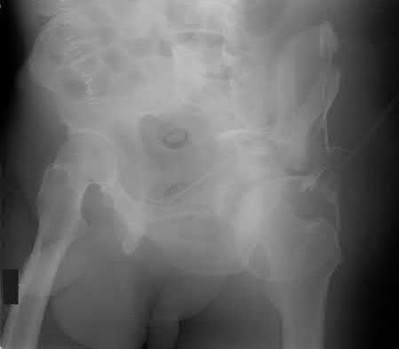

2. # A 35-year-old woman is involved in a head-on collision while driving. Initial radiographs are shown in Figures 8a and 8b. Injury to what vessel increases the risk for osteonecrosis of the injured bone?

5. Artery of the tarsal sinus Corrent answer: 4

The patient has a Hawkins type III talar neck fracture-dislocation with a risk of osteonecrosis ranging from 69% to 100%. Anatomic studies have shown that the artery of the tarsal canal supplies the lateral two thirds of the talar body.

The other vessels listed provide no significant contribution to the talus.